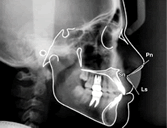

Computerized Orthodontic Diagnosis

Our office has provided computerized orthodontic diagnosis and treatment planning to our patients for over 7 years. With this software, we can trace your x-rays take your measurements, compare them to norms and more easily visualize the desired results of treatment. We can also store and have ready access to your before and after photos for comparison.Below are some views of the software.